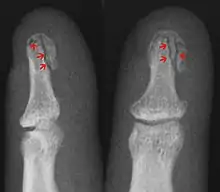

| Avulsion fracture | A fragment of bone is separated from the main mass (image shows a Busch fracture) | |||